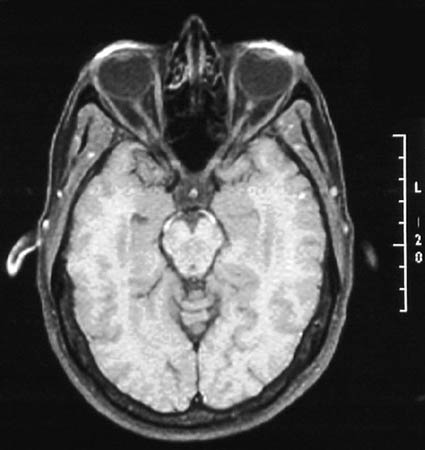

| The location of the optic nerves extending to the optic chiasm is shown in the MRI scan above. Normal optic nerve in cross section is shown below. Note the surrounding layer of dense connective tissue, or optic nerve sheath, which is essentially an extension of dura from cranial cavity. |

[Image contributed by Nick Mamalis, MD, University of Utah]